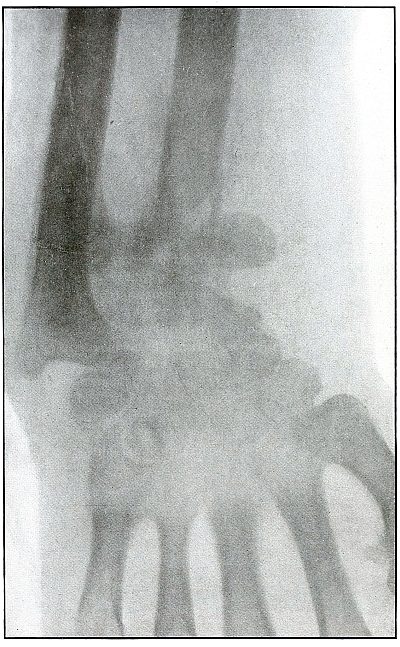

[Pg 94]

Plate 42.

[Pg 95]

Rifle—Plate 42.

UPPER EXTREMITY.

Gunshot Fracture of the Wrist.

This plate, presenting a lateral view of the wound shown in

plate 41, shows considerable deformity of the

joint, after four months’ treatment, which was even more marked two

months later, when the case was discharged with an ankylosis of the

wrist joint, contracture of the flexor tendons of the fingers, and

slight flexor function of the thumb, permitting apposition with the

first finger.

The result, while leaving much to be desired, preserved a function of

the hand vastly superior to that of a forearm stump.

The treatment in such cases is always courageously conservative, with

amputation only as the extreme measure to save life, with risks of

judgment in favor of conservatism.

Corrective measures may be employed after management if the treatment

of the infection is successful and when the case passes out of the

military category. It is not possible, during a long infection, to

maintain better position in such cases.